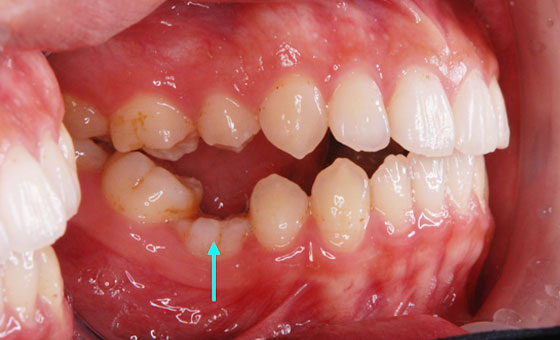

先天性欠如を 矯正治療で改善させた症例です。

歯列の中央(真ん中の軸)が先天的な欠損により片方の前歯で不均等になっていましたが、治療により上下の中央が調整されました。[治療期間:2年/治療費用:154万円]

成人になっても乳歯が抜けなかったため、乳歯を抜歯し。抜歯したスペースが完全に閉じ、かみ合わせも改善されました。

[治療期間2.5年/治療費用137.5万円]